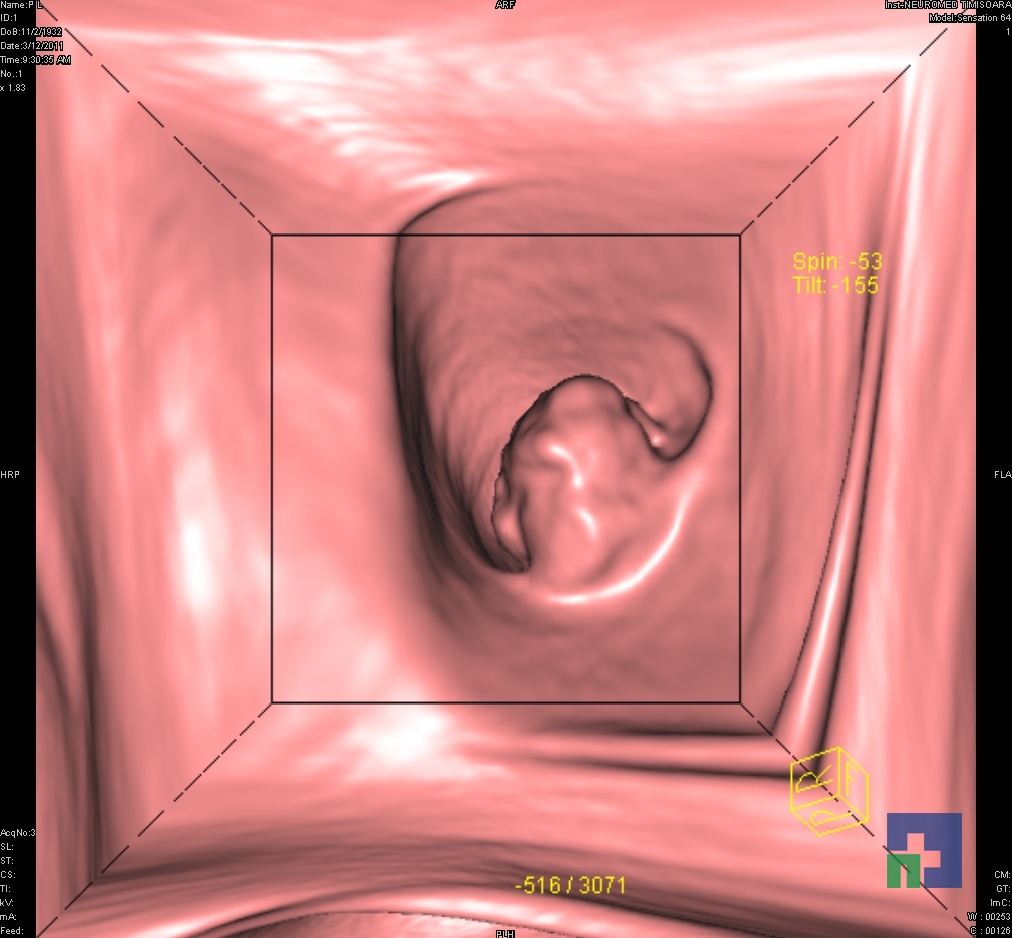

Examinare de rutină cerebrală, nativ și cu substanță de contrast (SDC) pentru diagnosticul:

- Accidentelor vasculare cerebrale ischemice sau hemoragice

- Tumorilor cerebrale